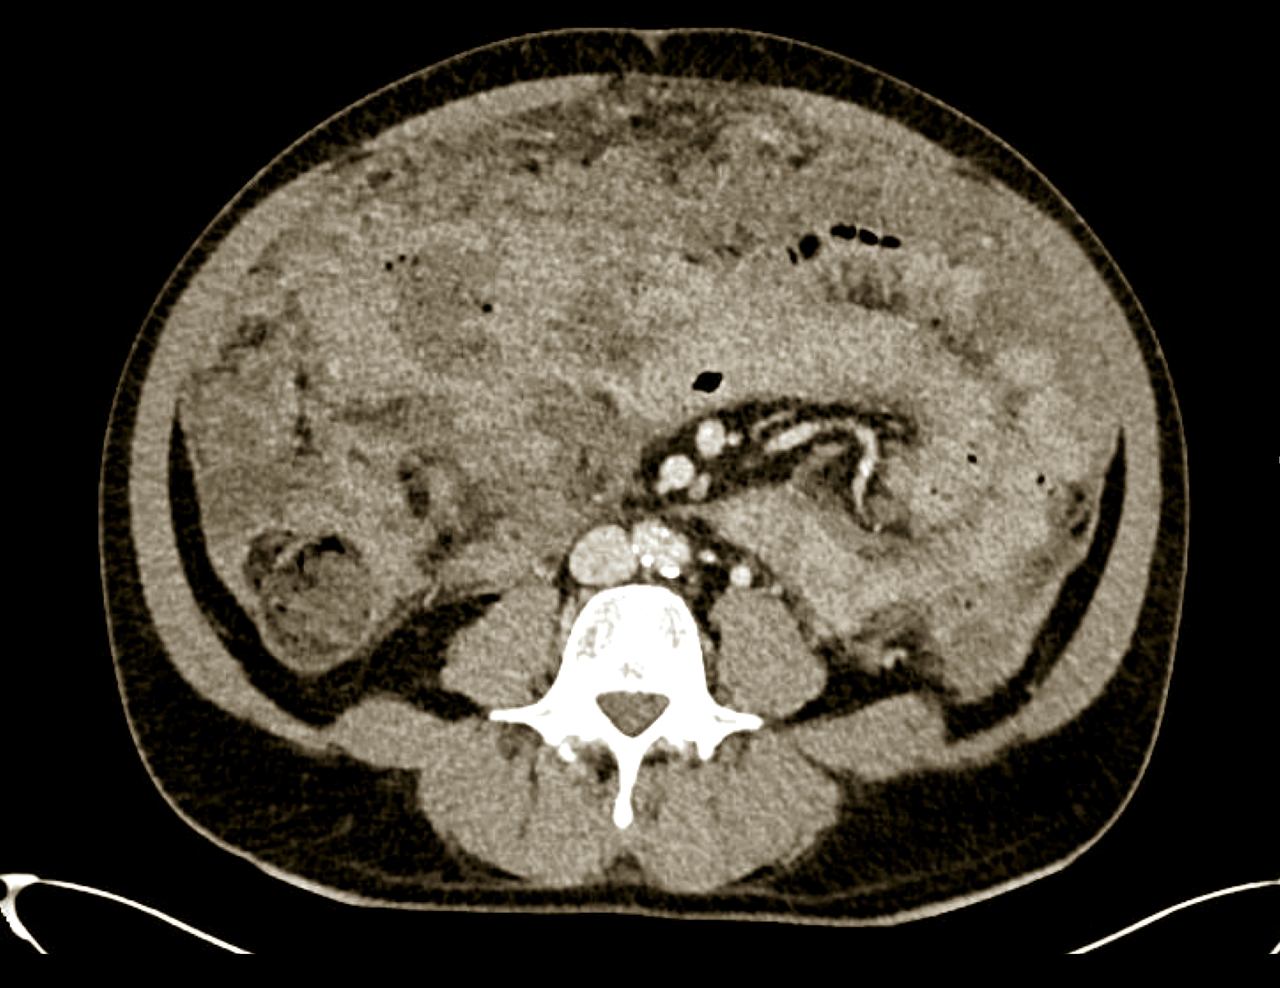

Quel est votre diagnostic ?

Il s'agit d'un lymphome de Burkitt.